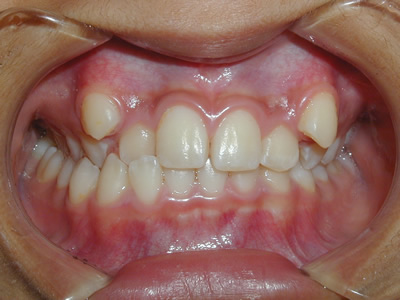

永久歯に交換するためのスペース不足による前歯のガタガタで、取り外しができる拡大床にて上下顎の幅を拡大した後、上顎の前歯をマルチブラケット装置で並べました。治療の期間は1年9か月でした。

終了時